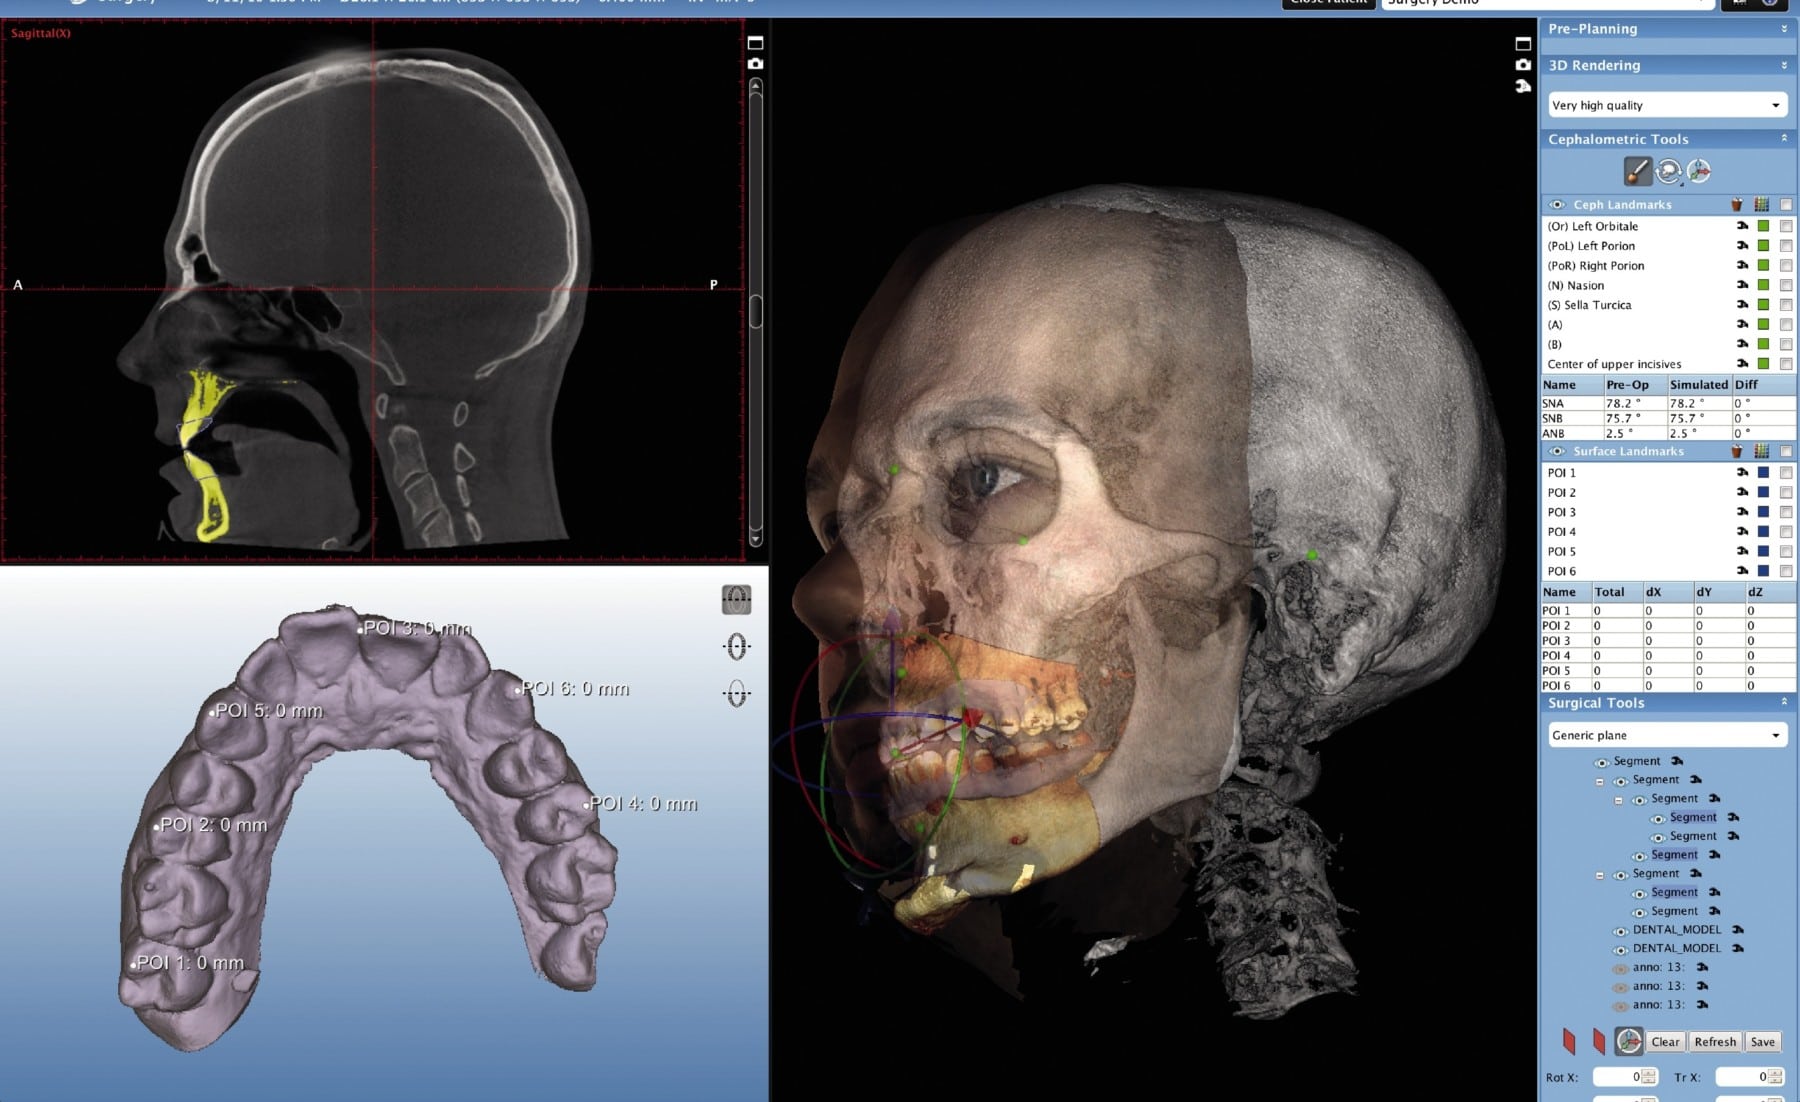

Before addressing pricing, a critical technical distinction must be established: CBCT (Cone Beam Computed Tomography) fundamentally differs from structured light or laser triangulation systems. CBCT utilizes ionizing X-ray radiation and rotational gantry mechanics to generate 3D volumetric data. Structured light and laser triangulation are optical surface capture methods employed in intraoral scanners (IOS), not CBCT systems. Conflating these technologies indicates a fundamental misunderstanding of dental imaging physics. This review focuses exclusively on CBCT engineering economics.

CBCT pricing in 2026 is dictated by quantifiable engineering parameters, not marketing tiers. The table below dissects cost drivers based on component-level specifications and their clinical/operational impact:

Pricing differentials directly correlate with measurable workflow gains. High-precision systems (>$100k) demonstrate ROI through:

In 2026, CBCT pricing is a direct function of underlying engineering choices impacting clinical fidelity and operational economics. Premium systems command higher prices due to quantifiable reductions in stochastic error (noise), systematic error (artifacts), and process variance (scan time/reliability). Labs and clinics must evaluate cost per diagnostically acceptable scan (CPDAS), not unit acquisition cost. Systems enabling sub-0.1mm geometric accuracy, AI-driven workflow compression, and spectral artifact suppression deliver superior ROI through reduced rework, higher throughput, and expanded clinical capability – principles rooted in metrology and systems engineering, not marketing narratives.